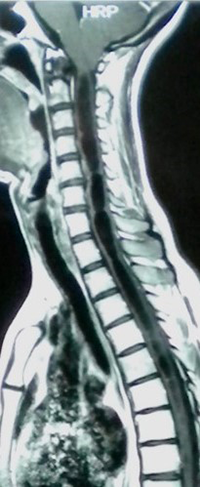

La siringomielia (SM) es una dilatación quística de la médula espinal de forma, tamaño y extensión variables, secundaria a una obstrucción en la circulación normal del líquido cefalorraquídeo (LCR), localizada en la fosa posterior (Chiari, quistes aracnoideos, etc.) o en el canal espinal (aracnoiditis, espondilosis, etc.) 1 (Figura 1).

Figura 1: RM sagital ponderada en T1 que muestra una siringomielia cervicodorsal causada por una malformación de Chiari tipo 1.